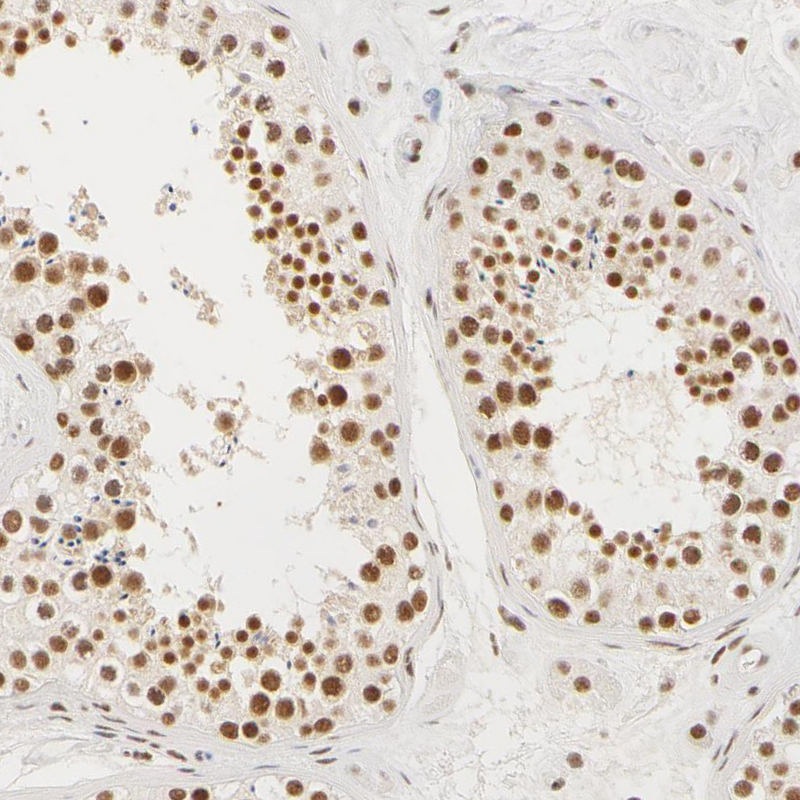

Immunohistochemical staining of human cervix, uterine shows moderate nuclear positivity in keratinocytes.